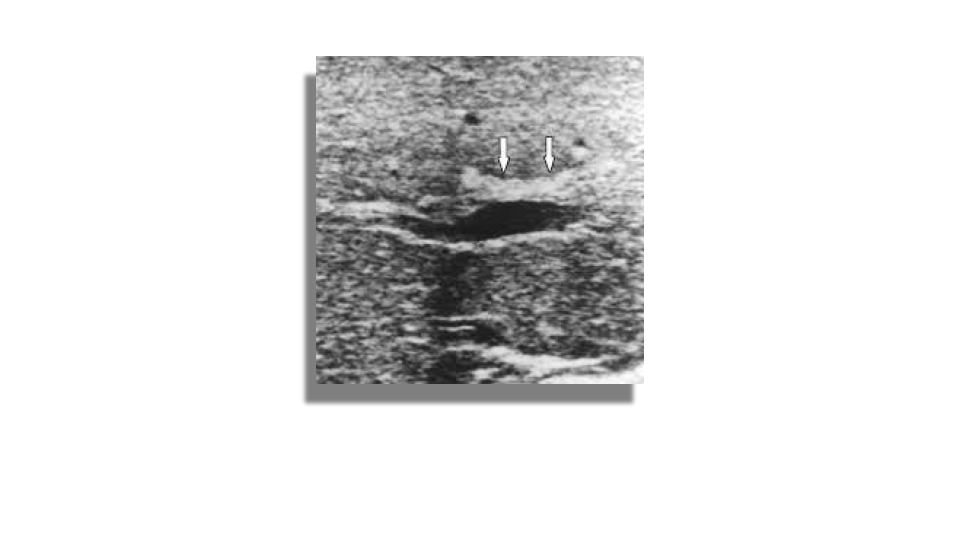

BIliary atresia is a congenital obliteration of the extrahepatic biliary system which results in obstruction of bile flow. The incidence in the US is 1 per 10,000 -15,000 live births. It is more common in asian populations. Typical symptoms are jaundice, dark urine and light stools. Sonography can be used to rule out other causes of jaundice, occasionally ultrasound can show an absent or small gallbladder and the triangular cord sign which represent the fibrous remnant of the extrahepatic bile duct. HIDA scan is better at evaluating for biliary atresia.